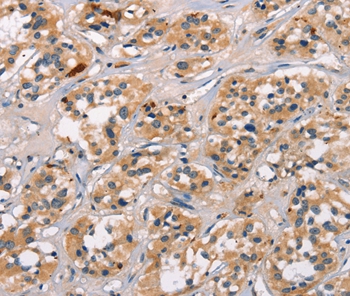

ATRN Antibody - N-terminal region (OAAB18786)

- Product NameATRN Antibody - N-terminal region (OAAB18786)